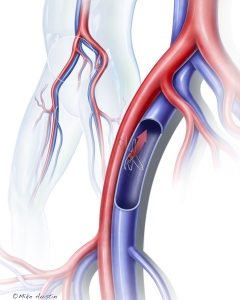

Welcome to my Patient and Professional Marketing page, where I harness the power of anatomical illustrations to educate and empower both patients and medical professionals. My unique approach combines artistry and education to convey complex surgical procedures and the utilization of medical devices in an easily understandable manner.